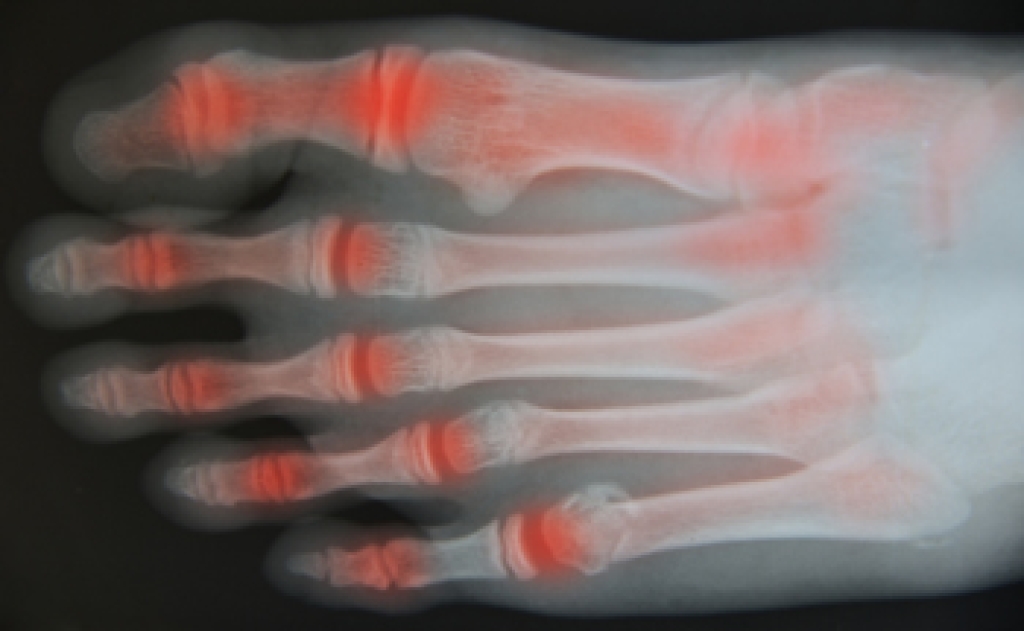

Achilles tendon injuries are diagnosed by a thorough physical evaluation, which can include an MRI. Treatment involves rest, physical therapy, and in some cases, surgery. However, various preventative measures can be taken to avoid these injuries, such as: